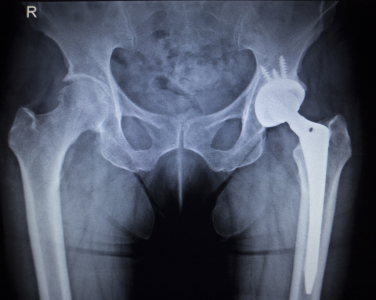

We provide specialized Cooled RF procedures for patients with chronic hip pain, particularly those with osteoarthritis or those seeking alternatives to hip replacement surgery.

This treatment is ideal for patients with chronic hip pain due to osteoarthritis or other degenerative joint conditions who have not responded to medications, injections, or physiotherapy and want to avoid or delay hip replacement surgery.

Cooled RF avoids the risks of major surgery, requires no hospital stay, involves minimal recovery time, and provides long-lasting pain relief without affecting joint structure.